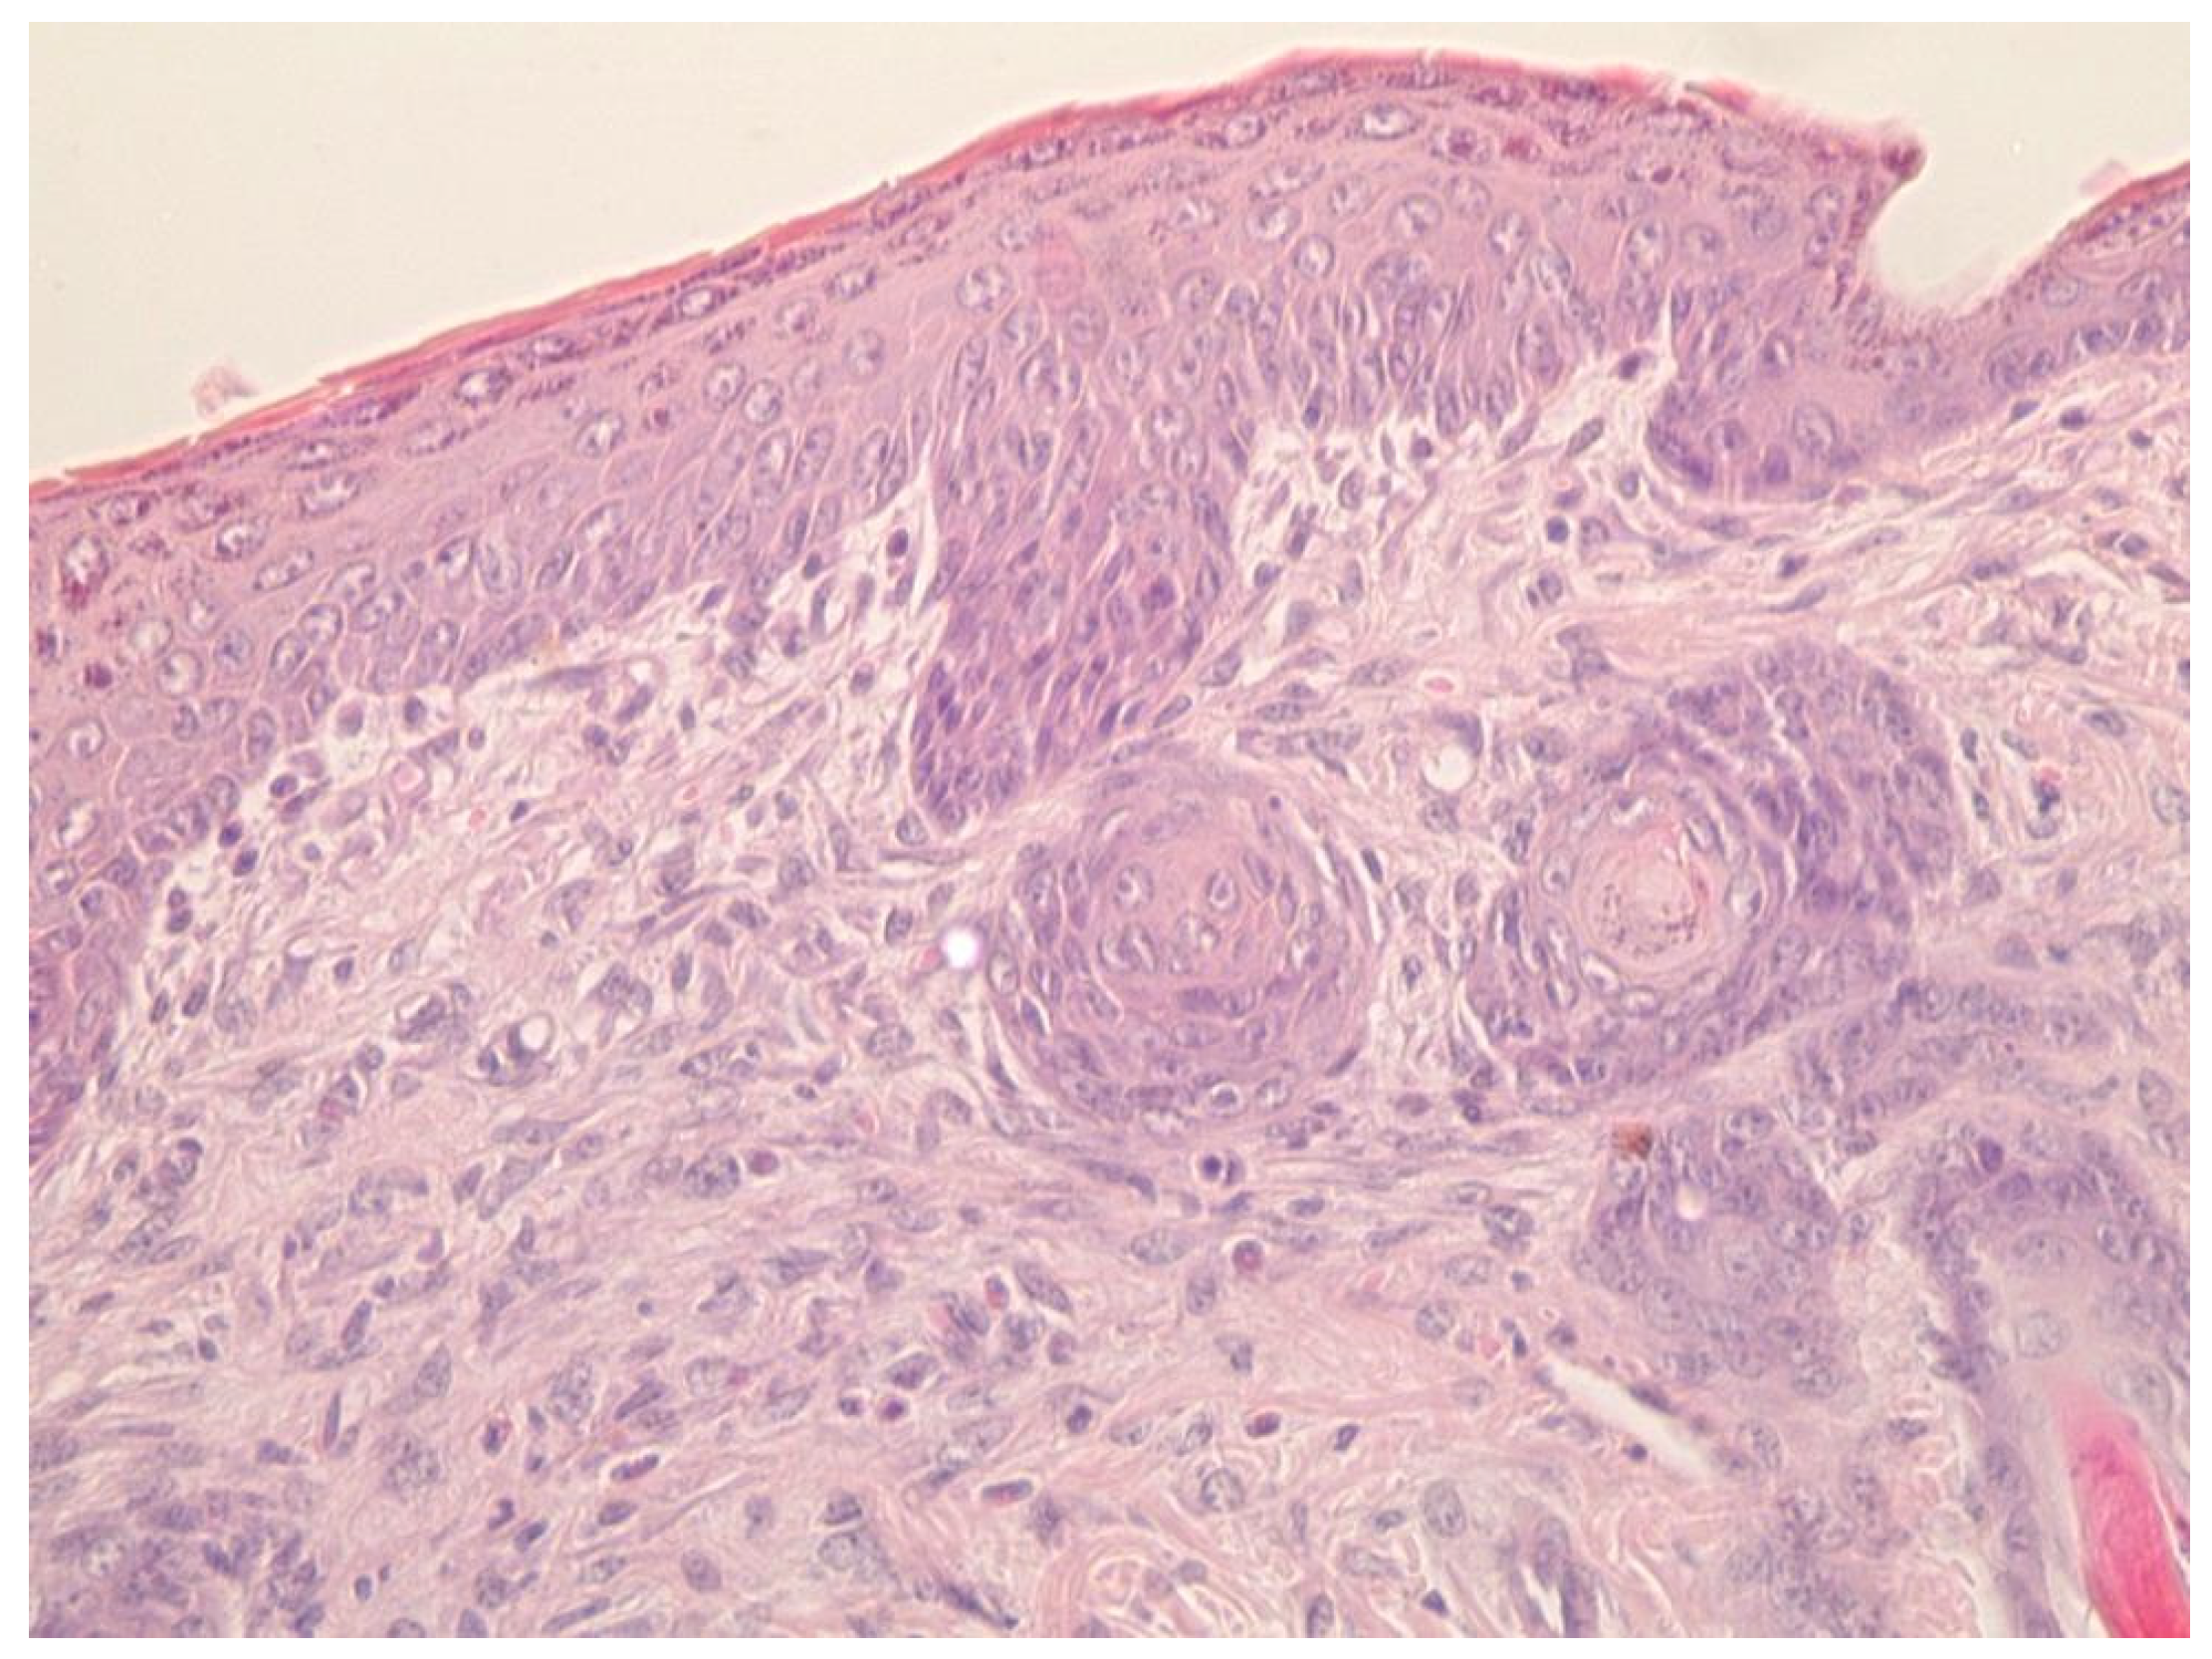

4.6. Investigation of Wound-Healing Ability of ZnO NPs Gels

4.7. Histological Research

- (1)

- A group treated with a gel of ZnO MPs and hydroxyethyl cellulose (control group);

- (2)

- A group treated with a gel of ZnO NPs modified with hydroxyethyl cellulose (experimental group).